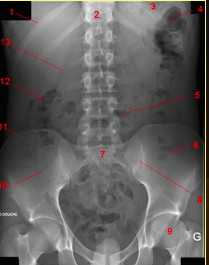

What does this show?

complete small bowel obstruction showing multiple air-fluid levels of varying size arranged in inverted U’s.

What does this show?

distended small bowel loops

bowel wall b/w loops is thickened and edematous (large white arrow)

No air is seen in the colon or rectum

What does this show?

complete colonic obstrucion

obstructing carcinoma in descending left colon = proximal air-fluid levels

absence of air distally in the rectum or sigmoid = complete obstruction

ileocecal valve is competent so there is no small bowel air